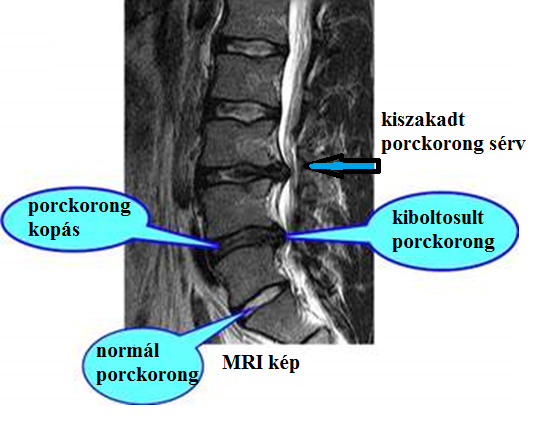

A beteg háta, dereka merev, egyre kevésbé tud lehajolni, a mellkas tágulása korlátozott, a hát görbültté válik. A felső háti rész fokozatosan meggörbülhet és a beteg púpossá válik. Számos ízületi megbetegedést az immunrendszer hibás programozása váltja ki. Az immunrendszer ilyenkor az ízületek részeit tévesen bakteriális fertőzésként ismeri fel és megtámadja azokat. Ezek a folyamatok vezethetnek olyan megbetegedésekhez, mint az artritisz vagy a Bechterew-kór, melynél az utolsó stádiumban a csigolyatestek egymásba olvadhatnak.  > Ez komoly betegség, és sokan az eleinte enyhe tünetek miatt nem is tudnak róla. A betegség lassan a gerincoszlop teljes elmerevedéséhez vezet, és a tudomány mai állása szerint nem gyógyítható. Mielőbb meg kell kezdeni az aktív gyógytornát és a nem-szteroid gyulladás gátlók szedését. A derék vagy háttájéki fájdalmat kopásos eredetűnek tartják, holott lehet, hogy Bechterew kór. Ennek megállapítása a HLA-B27 jelenlétének vizsgálata, amelyet a Synlab vérvétellel megállapíthat. A kór veszélyes hatása többek között a szív jobb kamrájának megnagyobbodása. Csontritkulás vizsgálata és kezelése. A csigolya összeroppanás hátterében leggyakrabban csontritkulás áll. Gerincsérvnél (foto) lézeres porckorong beavatkozás. Biológiai terápia.

> Ez komoly betegség, és sokan az eleinte enyhe tünetek miatt nem is tudnak róla. A betegség lassan a gerincoszlop teljes elmerevedéséhez vezet, és a tudomány mai állása szerint nem gyógyítható. Mielőbb meg kell kezdeni az aktív gyógytornát és a nem-szteroid gyulladás gátlók szedését. A derék vagy háttájéki fájdalmat kopásos eredetűnek tartják, holott lehet, hogy Bechterew kór. Ennek megállapítása a HLA-B27 jelenlétének vizsgálata, amelyet a Synlab vérvétellel megállapíthat. A kór veszélyes hatása többek között a szív jobb kamrájának megnagyobbodása. Csontritkulás vizsgálata és kezelése. A csigolya összeroppanás hátterében leggyakrabban csontritkulás áll. Gerincsérvnél (foto) lézeres porckorong beavatkozás. Biológiai terápia.

Gerinccsatorna-szűkület leírása és kezelhetősége a derék fájdalom enyhítésére. A derék merevsége miatt nehézkessé válik az előre hajolás, a fej fordítása. Derékfájdalom és kezelése. Tornagyakorlatok leírása és képi megjelenítése. Gerincsérv is fájdalmat okoz és neurológiai tünetekkel jár: zsibbadással, kisugárzó fájdalommal, tűszúrás-érzéssel, érzészavarral, esetleg inkontinenciával vagy széklettartási zavarral. A gerincsérv kialakulásának okai és kezelése.